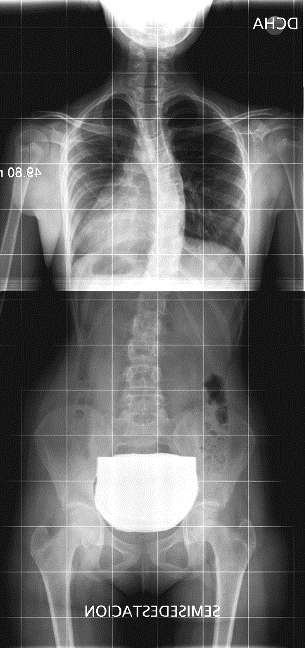

La escoliosis puede presentar una o varias curvas y en su evolución, no mejora (Figura 8). Por eso, se hace imprescindible su seguimiento con sucesivas telerradiografías, lo cual obliga, éticamente, a optimizar su estudio8.

Figura 8. Telerradiografía de escoliosis de una paciente a lo largo del tiempo. Mostrar/ocultar